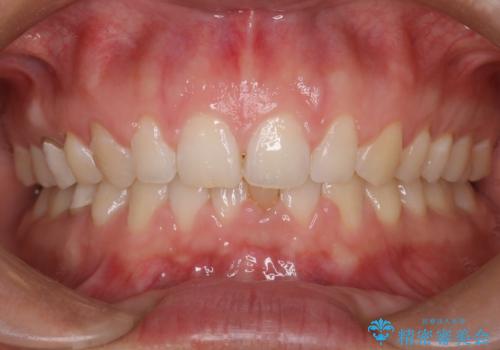

【前歯ブリッジ】下顎前歯の先天性欠如の補綴治療

- 晩期残存した下顎乳中切歯の変色を主訴に来院されました。

後続永久歯は先天性欠如しており、下顎前歯のブリッジにて補綴治療を行なっております。

色調も周りの歯に合わせることができ、患者さんには満足していただきました。